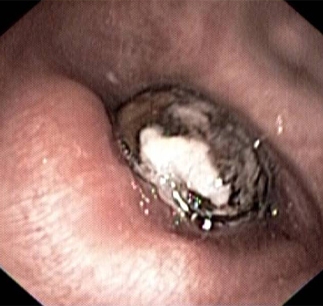

Imagen de broncoscopía en la que se muestra una semilla de níspero que obstruye por completo el bronquio intermedio

De la colección personal del Dr. S. Murgu y el Dr. H. Colt, University of California en Irvine Medical Center